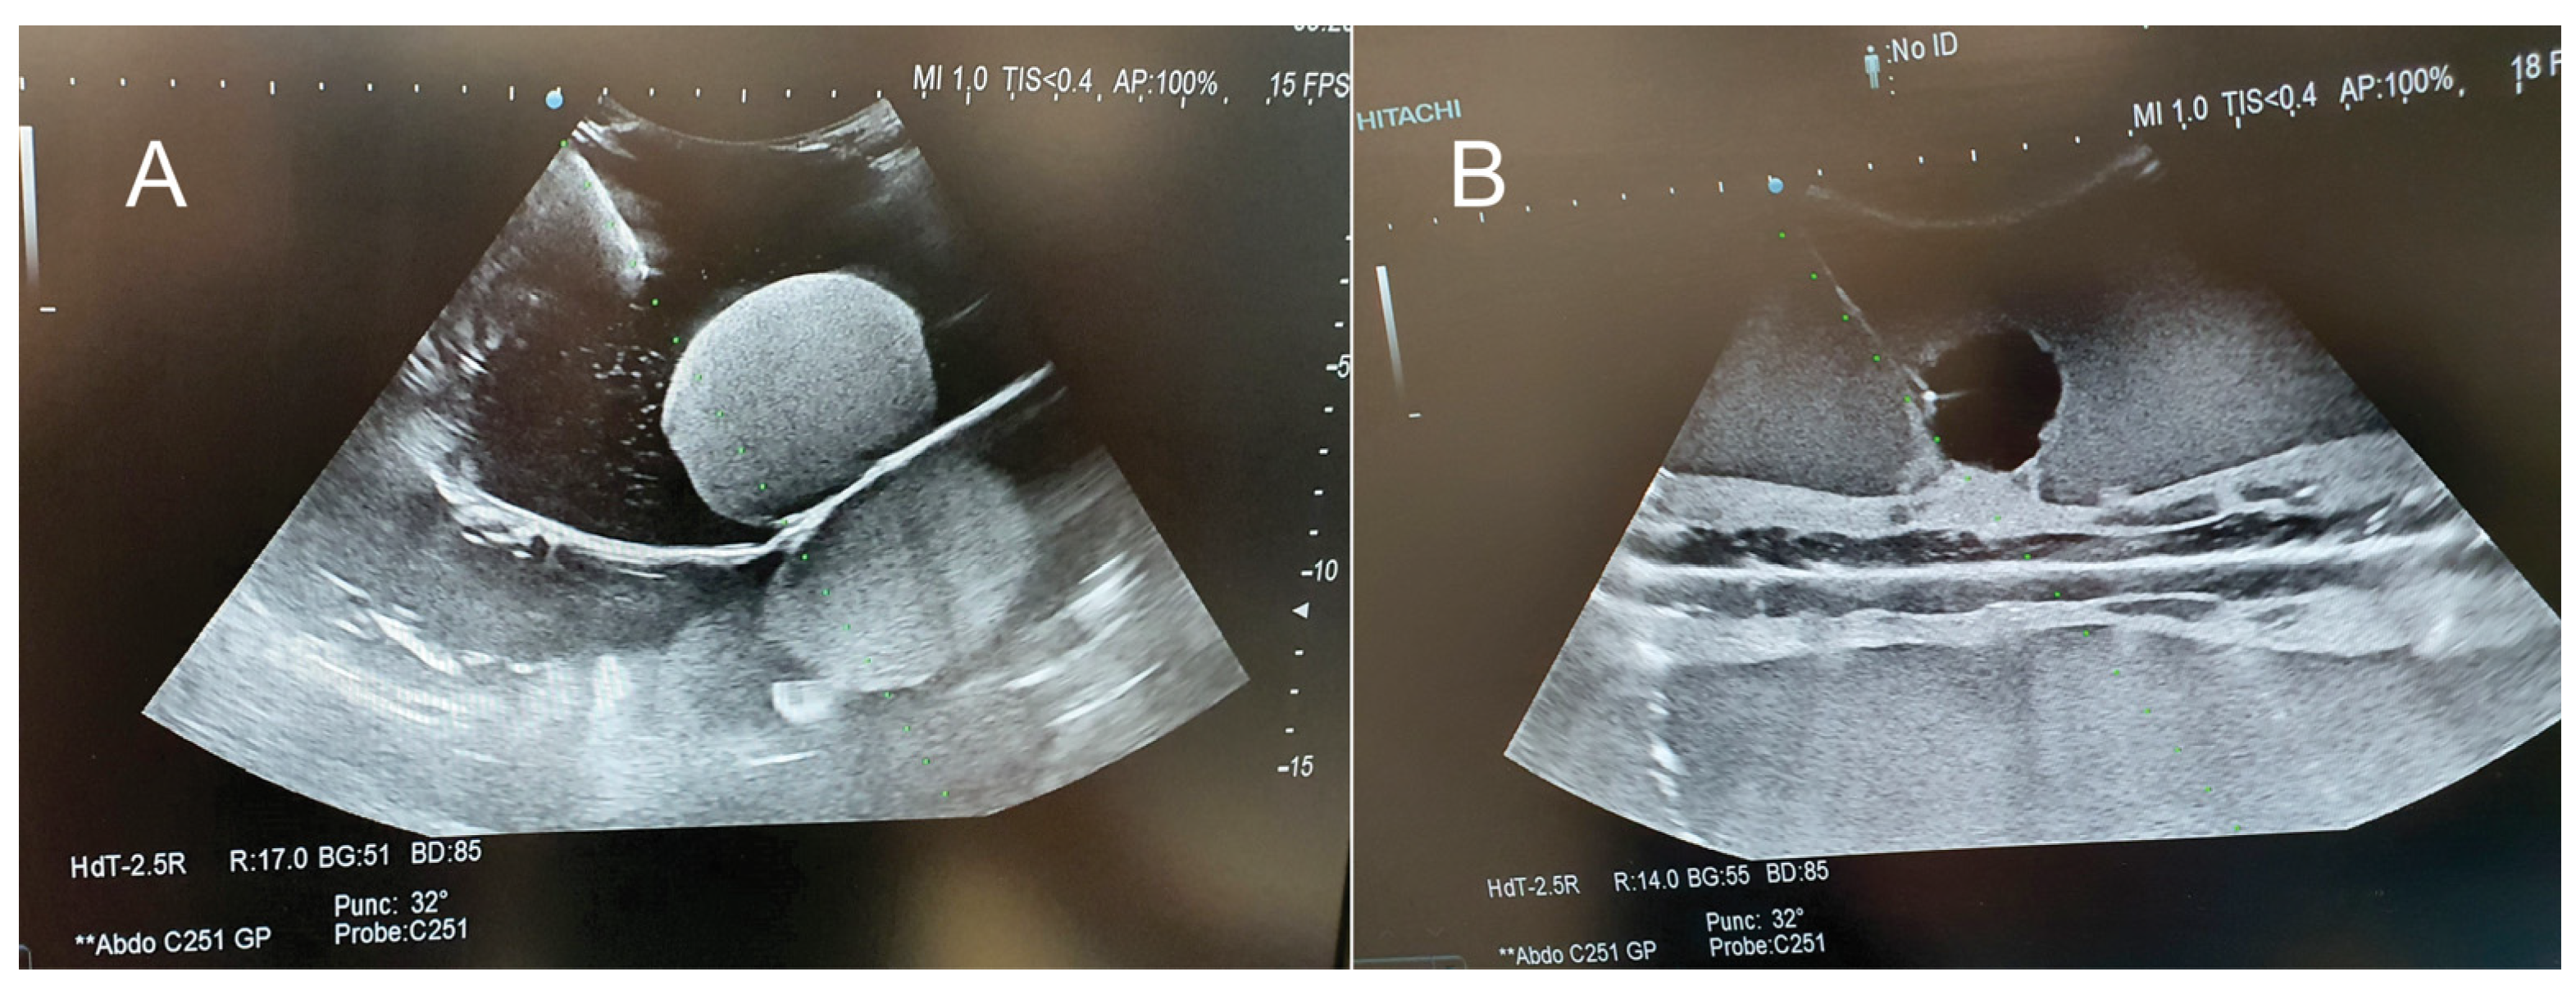

| Ultrasound | ![]() | ![]() | ![]() |